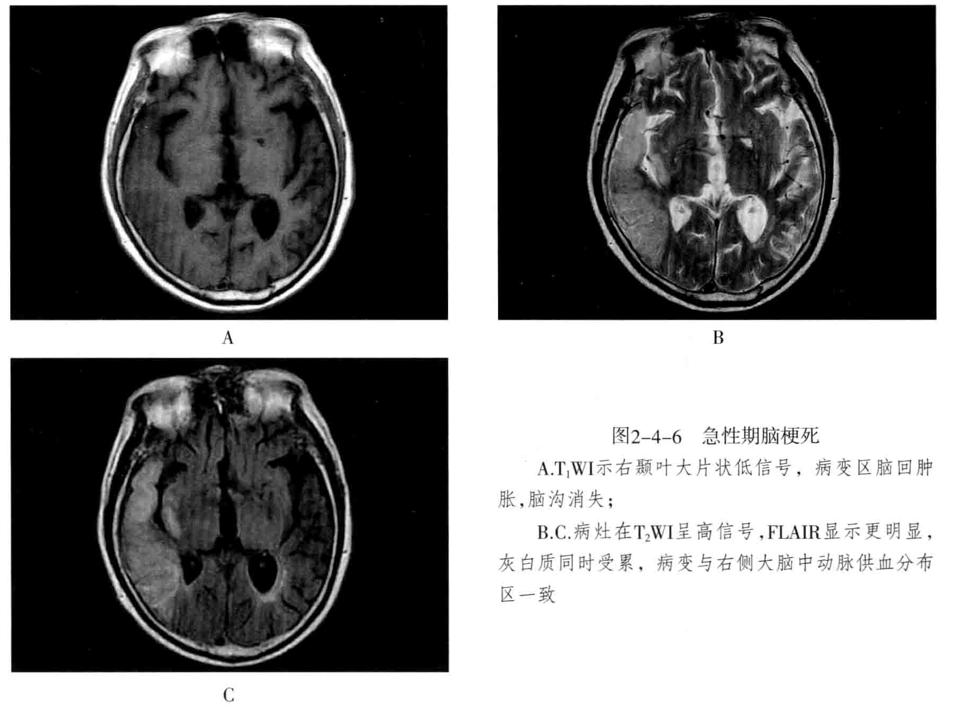

八、脑梗死:是一种缺血性脑血管疾病,常见有动脉闭塞性梗死和腔隙性脑梗死。主要病因为脑的大或中等管径的动脉发生粥样硬化,继发血栓形成,导致管腔狭窄、闭塞。以大脑中动脉闭塞最常见。脑梗死发生4-6小时脑组织发生缺血与水肿,继而脑组织出现坏死。1-2周后脑组织水肿逐渐减轻,坏死脑组织液化,梗死区出现吞噬细胞浸润,清除坏死组织,同时有胶质细胞增生和肉芽组织形成,8-10周后形成含液体的囊腔即软化灶。少数缺血性脑梗死在发病24-48小时后可因再灌注而发生梗死区内出血,转为出血性脑梗死。常见症状为偏瘫和偏侧感觉障碍、偏盲、失语等。

- CT表现为脑组织内低密度灶,梗死后2-15天为脑水肿高峰期,此时可有脑水肿表现;梗死1个月以后,相邻部位的脑室、脑池或脑沟扩大,出现脑萎缩表现。增强后梗死区可出现不均匀强化,呈脑回状、条状、环状或结节状强化。梗死区强化是由于血脑屏障破坏、新生毛细血管和血液灌注过度所致。

- MRI在脑梗死6小时之内,由于细胞毒性水肿,DWI可发现高信号,此后发生血管源性水肿、细胞死亡、髓鞘脱失、血脑屏障破坏,T1与T2弛豫时间延长。梗死后期,小的病灶不显示,表现为脑萎缩,大的病灶表现为软化灶。